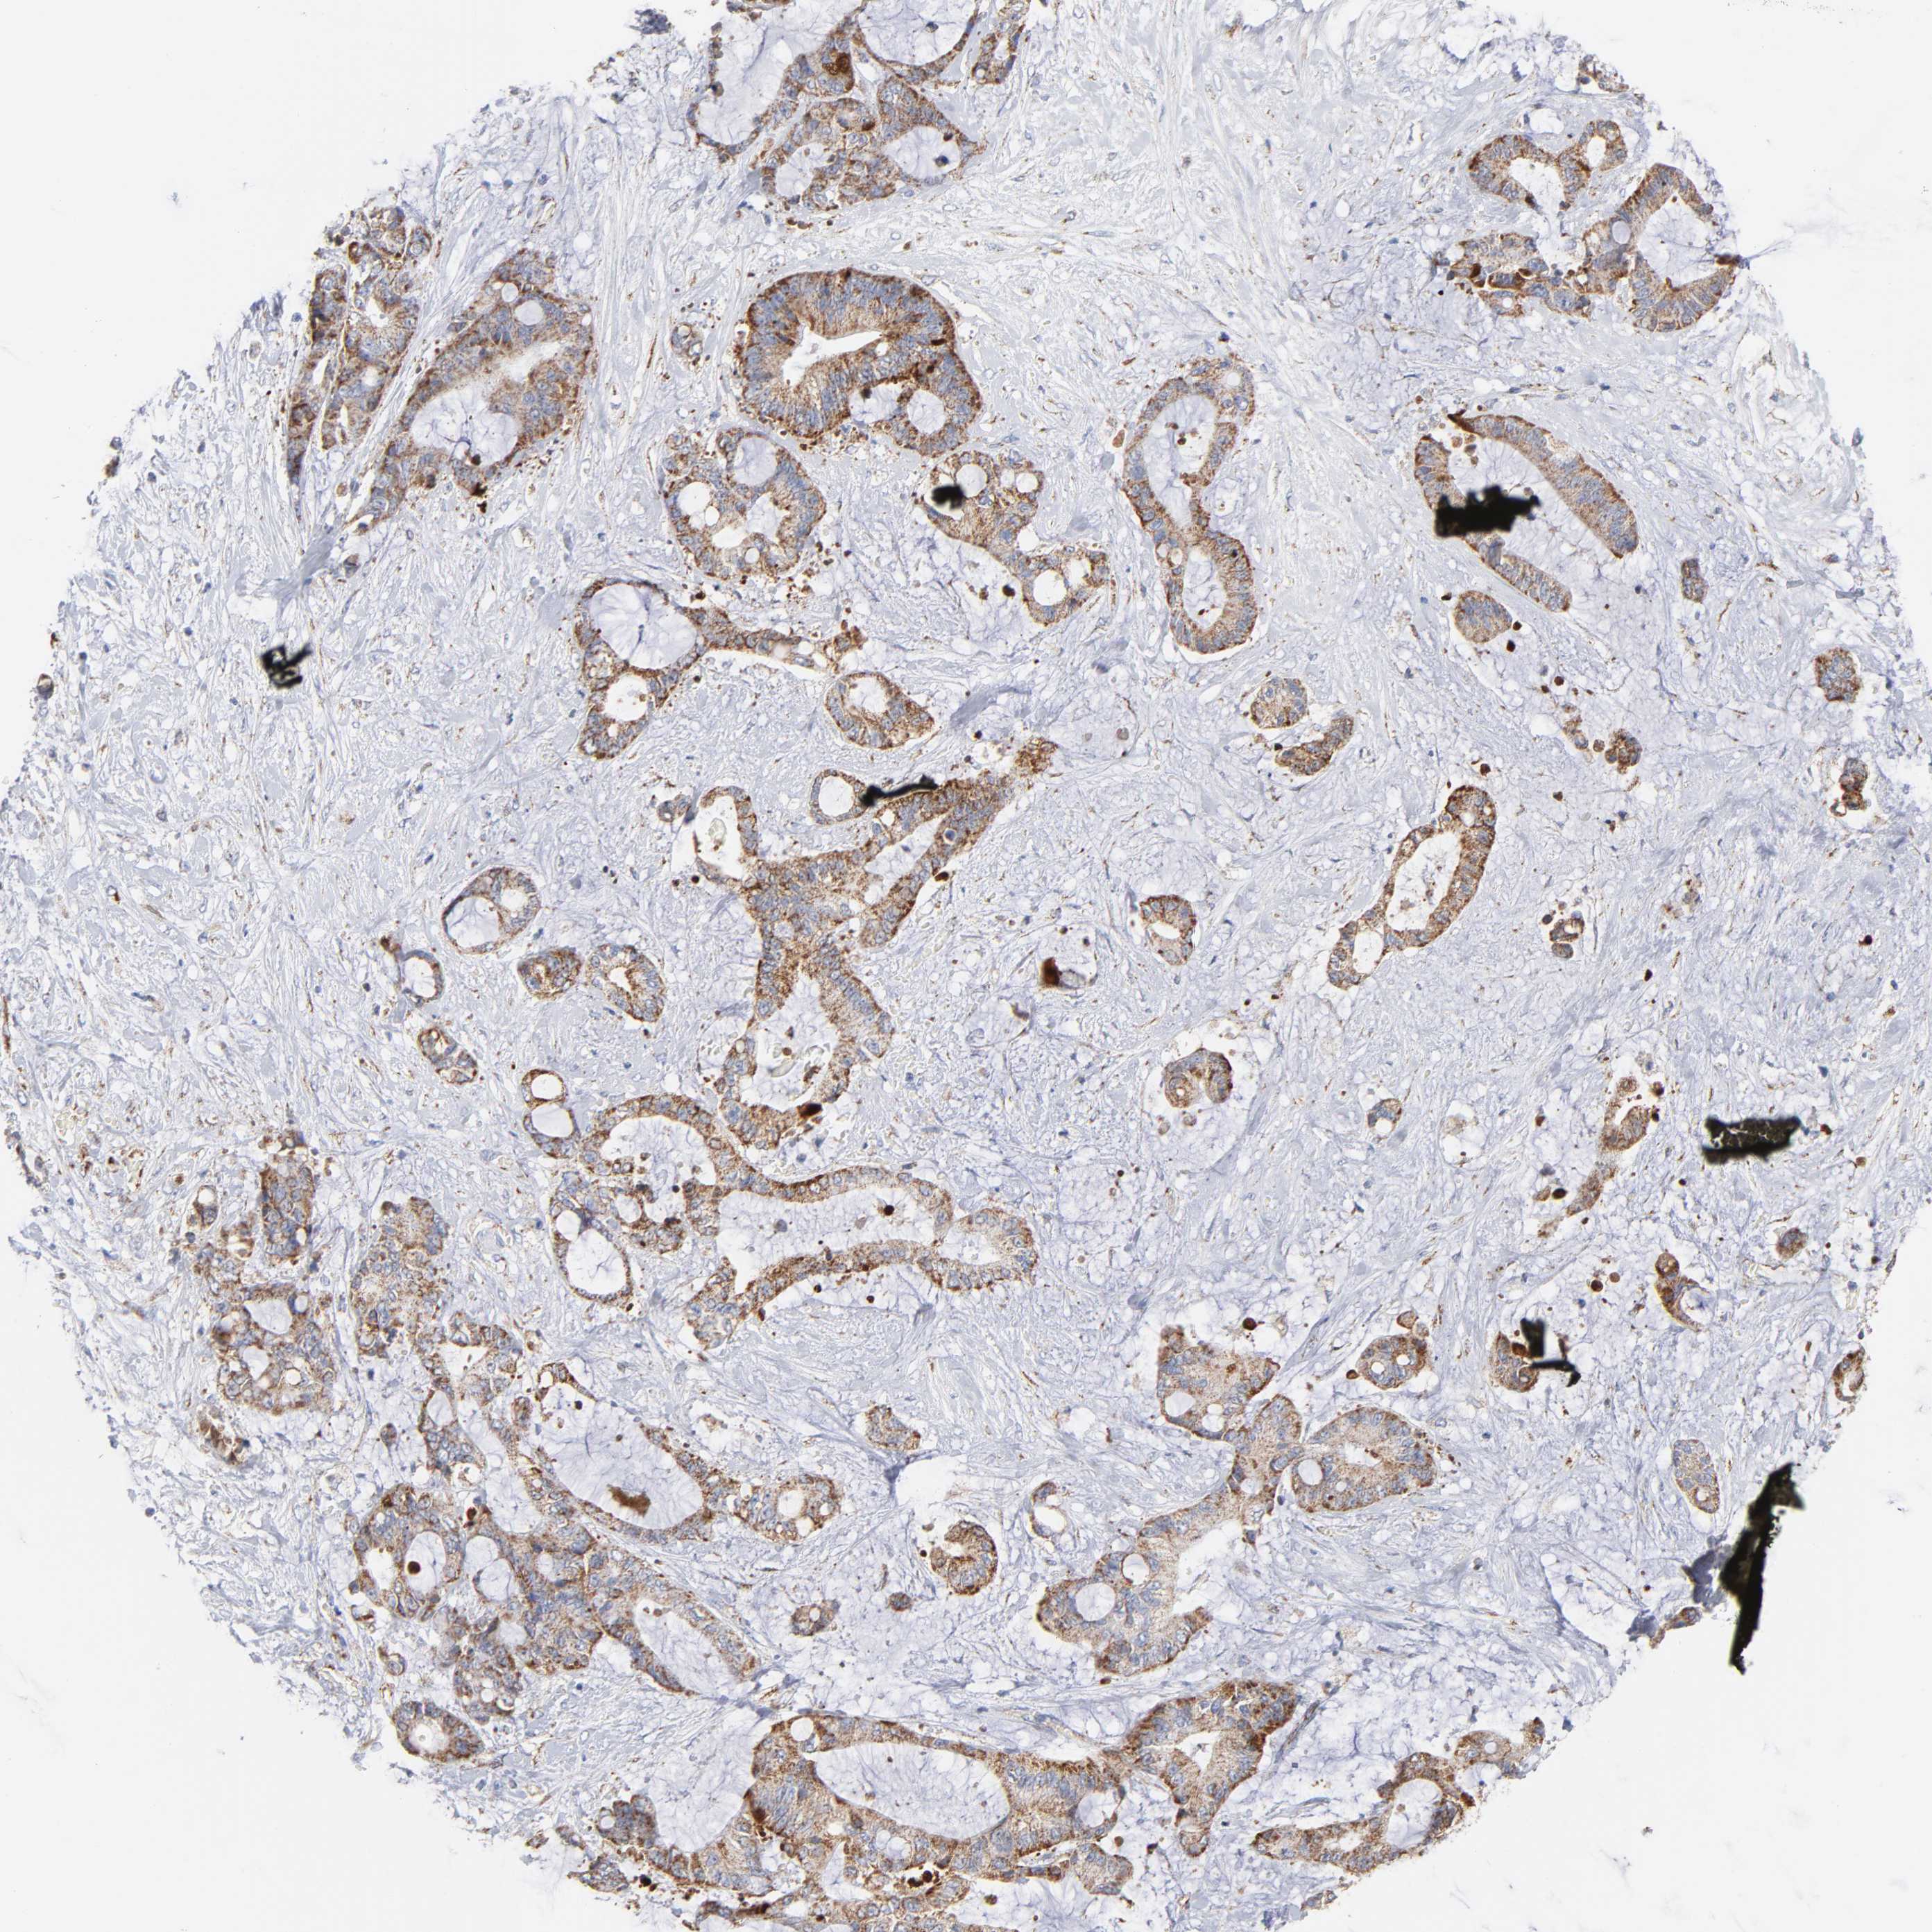

LIVER CANCER - Protein expressioni

A mouse-over function shows sample information and annotation data. Click on an image to view it in a full screen mode. Samples can be filtered based on level of antibody staining by selecting one or several of the following categories: high, medium, low and not detected. The assay and annotation is described here.

Note that samples used for immunohistochemistry by the Human Protein Atlas do not correspond to samples in the TCGA dataset.

Antibody stainingi

Antibody staining in the annotated cell types in the current human tissue is reported as not detected, low, medium, or high, based on conventional immunohistochemistry profiling in selected tissues. This score is based on the combination of the staining intensity and fraction of stained cells.

Each image is clickable and will lead to virtual microscopy that enables deeper exploration of all samples and also displays staining intensity scores, fraction scores and subcellular localization as well as patient and tissue information for each sample.

Antibody HPA001825

Antibody CAB003857

Staining

High

Medium

Low

Not detected

Intensity

Strong

Moderate

Weak

Negative

Quantity

>75%

75%-25%

<25%

None

Location

Nuclear

Cytoplasmic/membranous

Cytoplasmic/membranous,nuclear

Cholangiocarcinoma

Carcinoma, Hepatocellular, NOS